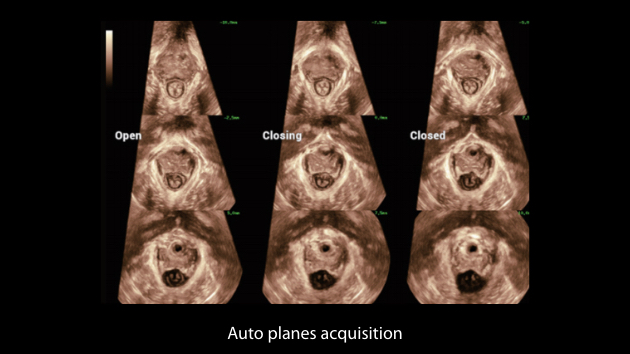

De Nuewa I9, speciaal ontworpen voor vrouwen en neonatale gezondheidszorg, biedt een innovatieve ervaring van binnenuit. Deze innovaties zijn ontwikkeld op basis van diepgaande inzichten in complexe klinische scenario's en bieden nauwkeurige en tijdige antwoorden, evenals een uitstekende effici?ntie en opmerkelijke gebruikerservaring.